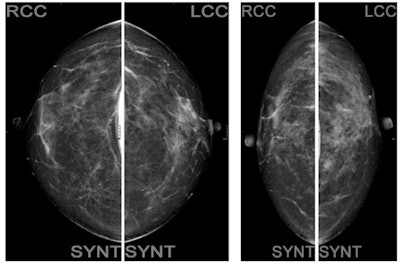

Standard algorithm versus low-dose algorithm in tomosynthesis.AEC is incorporated into radiographic and mammographic imaging systems. Its function automatically terminates exposure when a preset amount of radiation has been detected. Automatic exposure control systems help to provide a consistent optical density/signal-to-noise ratio between images, regardless of patient-centric factors such as size and density. They also help to reduce "dose creep" that can occur with inadvertent radiation overexposure by the radiographer.

The women were divided into two groups. The first group included 15 women undergoing standard protocol with standard configuration for the automatic exposure control (AEC) algorithm present on the mammography unit, including eight projections: four with digital mammography that included the breast implant and four with tomosynthesis (with synthetic image) using the Eklund maneuver, a modified compression technique that can be used for patients with augmented or reconstructed breasts postmastectomy.

In a second group of 38 women, a low-dose configuration of the AEC was activated to ensure a low-dose protocol.

If the Eklund maneuver is also performed in tomosynthesis mode, the woman is exposed to an average of 11 mGy in total. A low-dose configuration of the AEC is associated instead with an average glandular dose equal to 9.2 mGy total. This configuration allowed a maximum amount of radiographic information currently possible, lowering the dose by 15%, while maintaining adequate image quality, they pointed out.